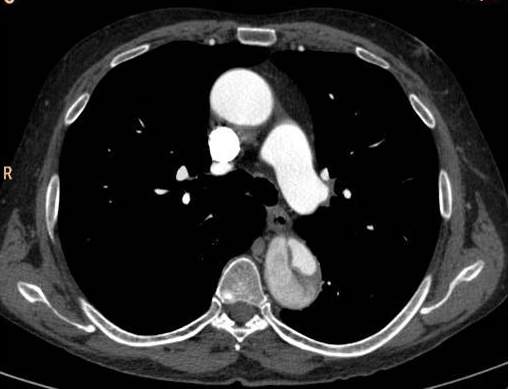

8.2.2.5. Aorta dissection

There are two main types of aorta dissection according to the Stanford classification: type “A” when the ascending aorta is involved, and type “B” when the dissection occurs distal to the origin of the left subclavian artery and it does not propagate to the level of ascending aorta or the aortic arch. The two types are distinguished because of their acute complications: type “A” dissection can cause the obstruction of the coronary trunks or, in case of a pericardial rupture, it can cause consequent pericardial tamponade and sudden death. Hence these cases require immediate surgical intervention with a cardiac surgical background. In contrary type “B” dissection can cause the acute obstruction of the abdominal aortic branches and can lead to life threatening conditions only in a subacute manner (intestinal ischemia, renal insufficiency). These conditions can also require surgical intervention (vascular surgery) but they rarely need immediate surgery. Both dissection types have the late stage complication of the development of aneurysm that occurs due to the weakened and constantly expanding vessel wall, which constitutes a growing risk for aortic rupture.

Primary diagnostic imaging is usually performed as an emergency examination, patients are often unstable, or gravely ill and in poor condition. Therefore, CTA is a most advantageous method; it can provide a diagnostic quality imaging even on a non-cooperative patient with. It is crucial to determine the type of dissection (A or B-), the involvement of the supraaortic and abdominal branches, the origin of the side branches, and the anatomy of the false and the real lumen and their permeability. A highly pulsating aortic root can cause diagnostic problems because of the vessel movement. The artifact caused by the moving arterial wall can mimic an intimal-flap, especially at the root of the ascending aorta. However, this can be avoided with ECG gated examination; hence patients with symptoms of acute coronary syndrome should be directed to a centum where ECG gated imaging is available.

Image

The lumen is divided by the detached intimal layer that can be followed from the origin of the left subclavian artery to the descending aorta.

The real lumen shows a fast filling and a more intense contrast enhancement,

while the false lumen shows a less intense contrast enhancement due to its decreased flow.

Fig. 26., 27., 28.: Type B aortic dissection CT angiography

On axial slices, an intima flap can be seen in the ascending aorta

The dissection spreads also into the lumen of supraaortic arteries

Fig. 29., 30.: Type A aortic dissection, ECG-gated CTA examination